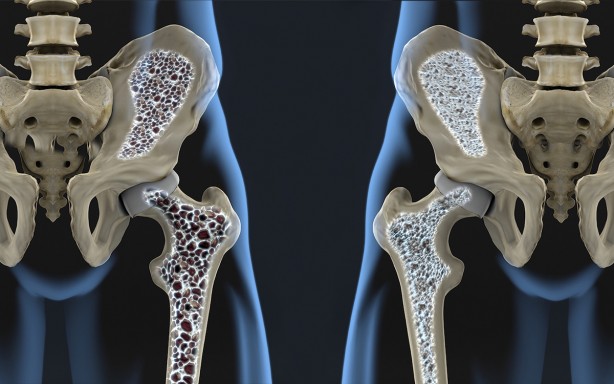

Her 3 kadının ve her 5 erkeğin 1’in görülüyor Günde sadece yarım saat ile kurtulabilirsiniz

Osteoporozu önlemenin mümkün olduğunu belirten Fizik Tedavi ve Rehabilitasyon Uzm. Dr. Öğr. Üyesi Elif Berber, “Osteoporoz önlemenin en önemli yolları D vitamini kullanmak, güneşlenmek ve kemiği güçlendirici egzersizleri uygulamaktan geçer. Yarım saatlik tempolu yürüyüşler şiddetle tavsiye edilir” dedi.